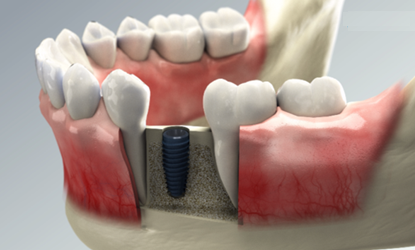

Step 01

tooth extraction

tooth extraction